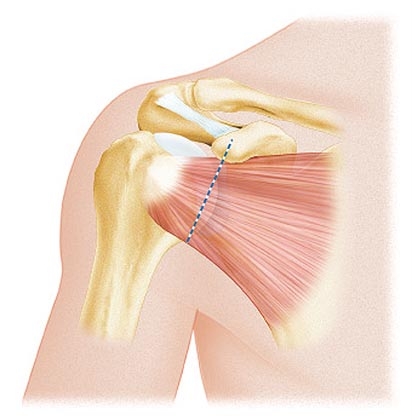

La perdita di contatto definitiva tra due capi articolari viene detta “lussazione” altrimenti se il contatto è perso solo temporaneamente si parla di “sublussazione”. Queste due condizioni sono comuni a tutte le articolazioni ma in particolar modo si verificano a carico della spalla e determinano il quadro di “instabilità articolare”.

Il trattamento chirurgico è strettamente correlato alla tipologia delle lesioni articolari ed al numero di lussazioni; la riparazione delle lesioni può avvenire in artroscopia (attraverso piccole incisioni si accede all’articolazione visualizzandola con una telecamera e con strumenti dedicati si procede alla riparazione dei tessuti) oppure a “cielo aperto” attraverso cioè un incisione della pelle di circa 8-10 cm (questa tecnica viene riservata generalmente nei casi di recidive o importanti lesioni che coinvolgono anche l’osso).